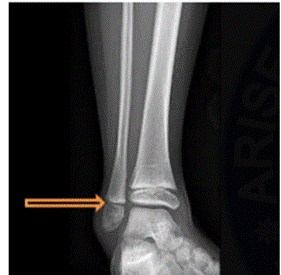

5. Subtopic: Types of Epiphyses

Question Number: 1

Non-Clinical question

The structure indicated by the arrow represents a specific type of epiphysis. What type of epiphysis is shown? (Orthopaedics)

Options:

- Pressure epiphysis

- Traction epiphysis

- Atavistic epiphysis

- Aberrant epiphysis

Correct Answer: A) Pressure epiphysis

Get the full explanation here: https://www.doctutorials.com/fmge/qbank/pyq/1000141